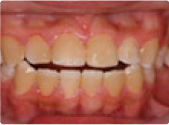

ムーシールドによる小児の矯正

治療前

治療後

この症例は、乳歯列(5歳)の受け口を「ムーシールド」という就寝中に使う矯正装置を使用して治療しました。受け口のままでいると、永久歯に生え変わったときにも受け口になりやすいです。 乳歯列の時から出来ることを積極的にすると、成人になって矯正をしなくてすむ確率も上がります。